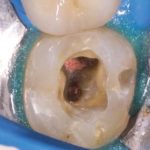

La perforazione del pavimento della camera pulpare dei pluriradicolati è una delle principali complicanze che possono presentarsi durante i trattamenti endodontici con prognosi spesso sfavorevole. In questo caso clinico si è optato per una terapia conservativa, che ha permesso di salvare l’elemento, utilizzando tecniche la cui efficacia è dimostrata da molti studi in letteratura.